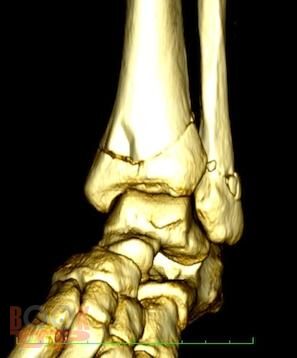

Учебно-методическое пособие содержит необходимую информацию для врачей по вопросам профилактики и лечения последствий тяжелых повреждений области голеностопного сустава. В Пособии представлены условия развития тяжелых статико-динамических осложнений при травмах голеностопного сустава, особенности осложнений при последствиях переломов дистального суставного отдела костей голени. Особое внимание уделено механизму развития посттравматического плоскостопия при повреждениях области голеностопного сустава.

В пособии обобщен более, чем 30-летний опыт лечения пациентов с последствиями тяжелых повреждений области голеностопного сустава.